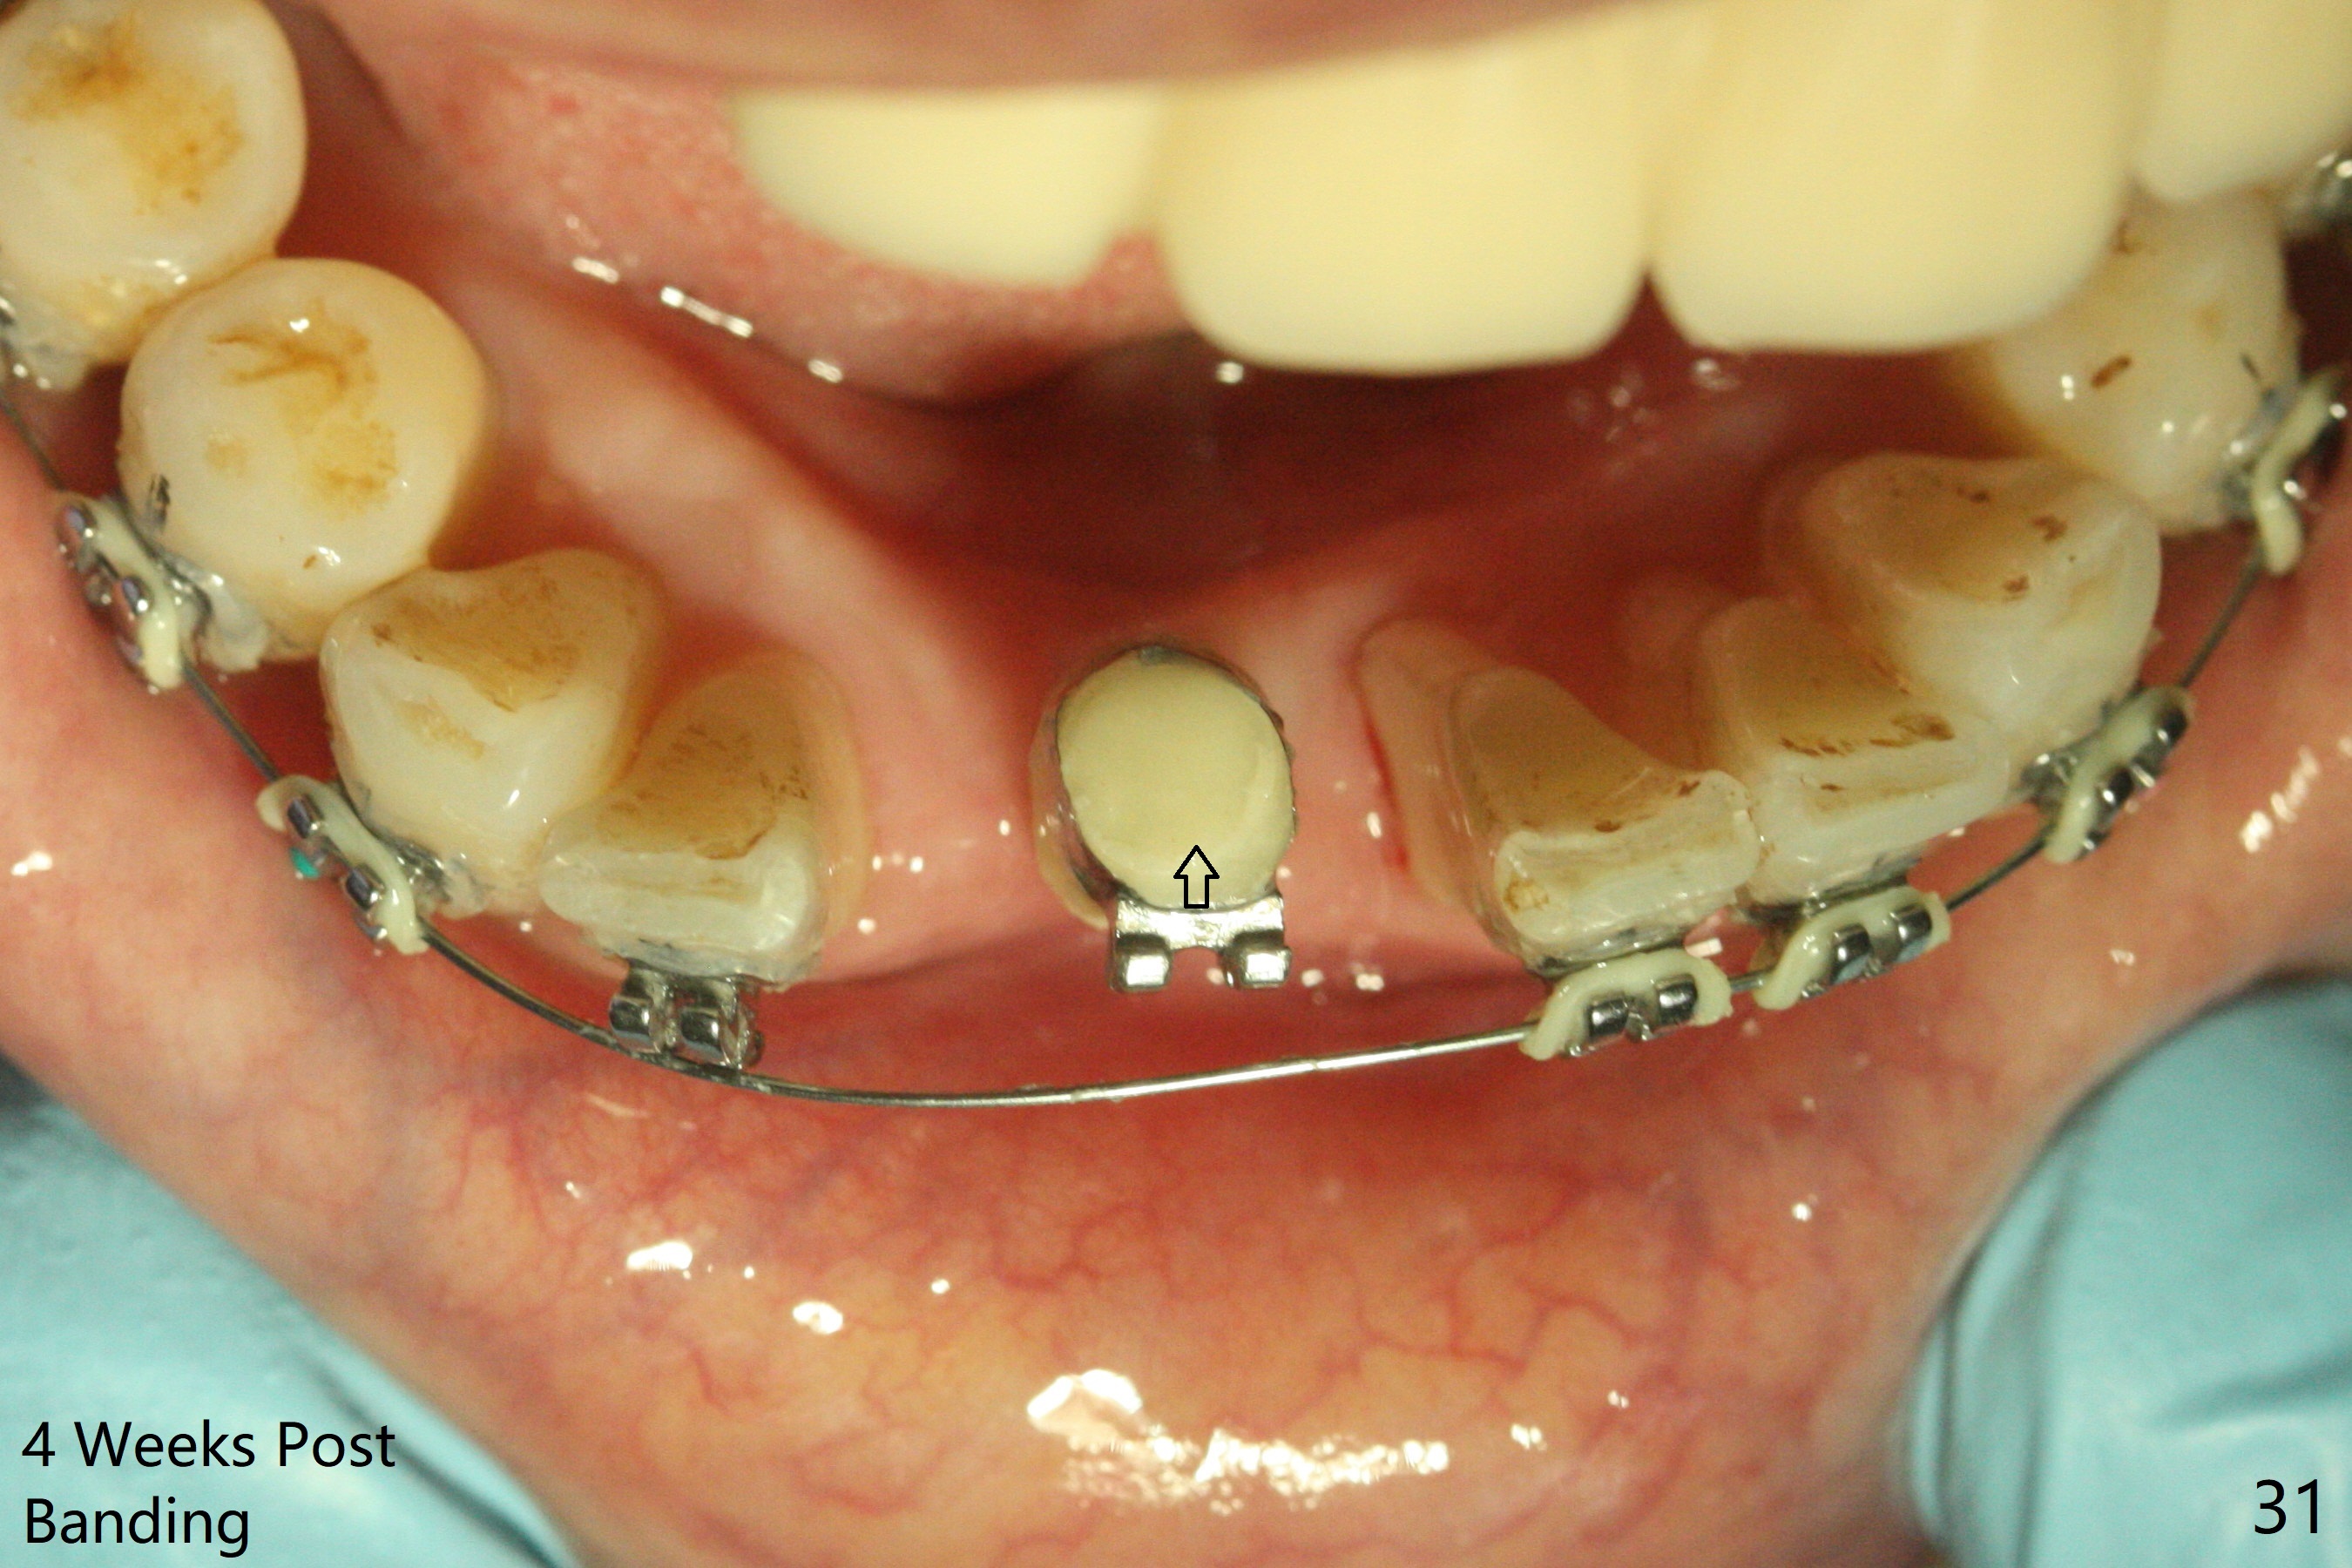

56岁女十分恐惧治疗,缺失右下1,其余切牙由于骨质吸收颊侧移位(图一:1,2),但是她不愿意拔除,同意右下1种植,牙周骨手术,植骨;植体整合后作为支抗,矫正移位下门牙。为了防止忘记舌侧瓣分离,先做舌侧切口(图二),然后颊侧瓣松弛分离(图三),包括使用前牙隧道刀(图四)切断颊侧骨膜,松弛到颊侧瓣能向舌侧牵拉3-4毫米(图五),舌侧瓣骨膜下广泛,深部分离(好像不能切断骨膜,图六),放置导板,磨平狭窄的牙槽嵴(图七:O(osteotomy)),植入2.5x12(4)毫米一段式植体(图八:故意舌侧植入,以便以后矫正),在颊侧骨板打多个出血洞(图八:箭头),然后把在平的器皿上形成的粘性骨板(sticky bone,图九),放置于植体和移位切牙周围(图十),接着使用消毒过的橡皮障punch(图十一(纸头相当于PRF膜;事先给助手示范))在三个PRF膜(图十二)打洞,套在植体和门牙上(图十三: 箭头),防止膜(图十四)和骨块(图十五,十六:*)移位,最后还必须使用最原始方法牙周敷料保护伤口(图十七)。术后9天,舌侧牙周敷料脱落,伤口稍微裂开(图十八)。术后18天撤除敷料,伤口裂开处有新鲜肉芽组织生长(图十九(*:下面是填入的骨粉,将是增宽的牙槽嵴(如果你是乐观主义者)),二十)。病人十分感激我们帮助她度过难关。她的确有sleep apnea,否定tongue thrust。术后三个月植体周围没有明显骨质吸收(图二十一至二十三),左下1,2轻度反合(图二十四),植体周围软组织健康(图二十五),5-5安置矫正器(图二十六,二十七,12 niti)。一周后下切牙向舌侧移动(图二十八),左下1,2反合纠正(图二十九)。再一周变化不大(图三十),植牙圈有些松动,两周后将重做临时牙冠,槽往舌侧移动。结果病人提前回来,植牙槽舌侧移位。一周后右下2不适(图三十一),尝试近中牵引(图三十二)。